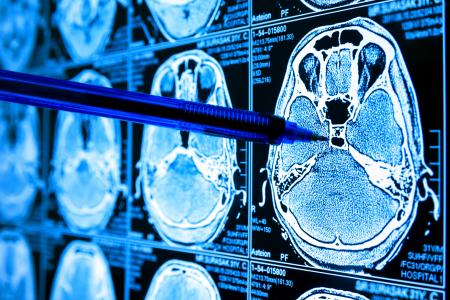

GLIOBLASTOME : Bloquer l’enzyme clé qui contrôle sa croissance

Cibler cette enzyme clé qui contrôle un vaste réseau de protéines importantes dans la division et la croissance cellulaires ouvre la voie à une nouvelle classe de médicaments qui pourraient empêcher le développement du glioblastome. C’est ce que propose cette équipe de cancérologues du Princess Margaret Cancer Centre, du Hospital for Sick Children (SickKids) et de l'Université de Toronto : ils apportent ici, dans la revue Nature Communications, une première preuve preuve de concept : l'inhibition chimique in vitro de l'enzyme PRMT5 sur des lignées de cellules humaines de glioblastome parvient à stopper la croissance tumorale.

D’autres équipes avaient déjà suggéré que l’inhibition de PRMT5 peut être le moyen de cibler les tumeurs cérébrales, cependant c’est la première étude à tester cette stratégie in vitro sur des lignées de cellules dérivées de tumeurs de patients, précisément sur des cellules précurseurs, à l'origine de la croissance du glioblastome. L’équipe montre que l’inhibition de PRMT5 arrête une cascade de protéines impliquées dans la division et la croissance cellulaires. De plus, la technique permet de surmonter le défi de la variabilité génétique observée dans ces tumeurs : en ciblant les processus impliqués en amont de la croissance tumorale, les scientifiques évitent la difficulté posée par la variabilité tumorale individuelle de chaque patient qui peut constituer un obstacle au traitement.